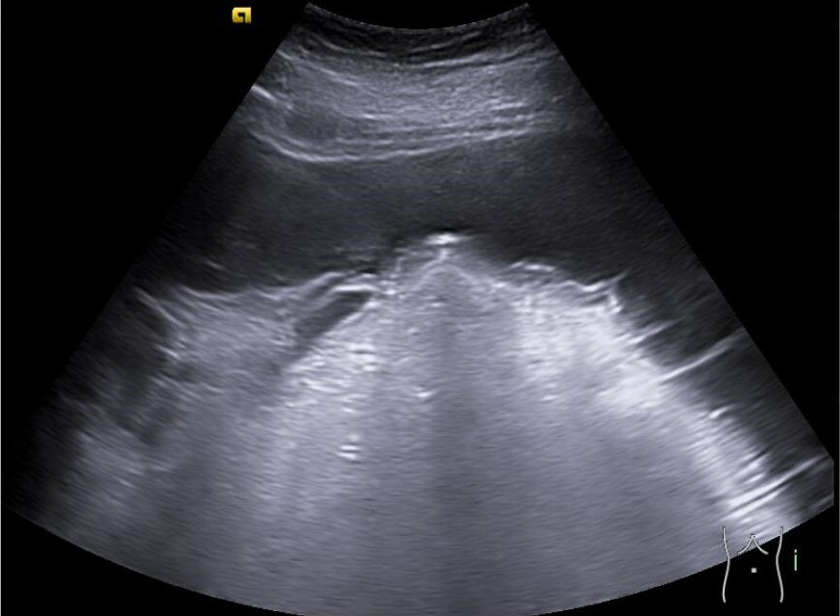

Se realiza ecoPOCUS y se objetiva imágenes anecogénicas en todas las zonas declives, en ambos flancos e hipogastrio y derrame pleural izquierdo.